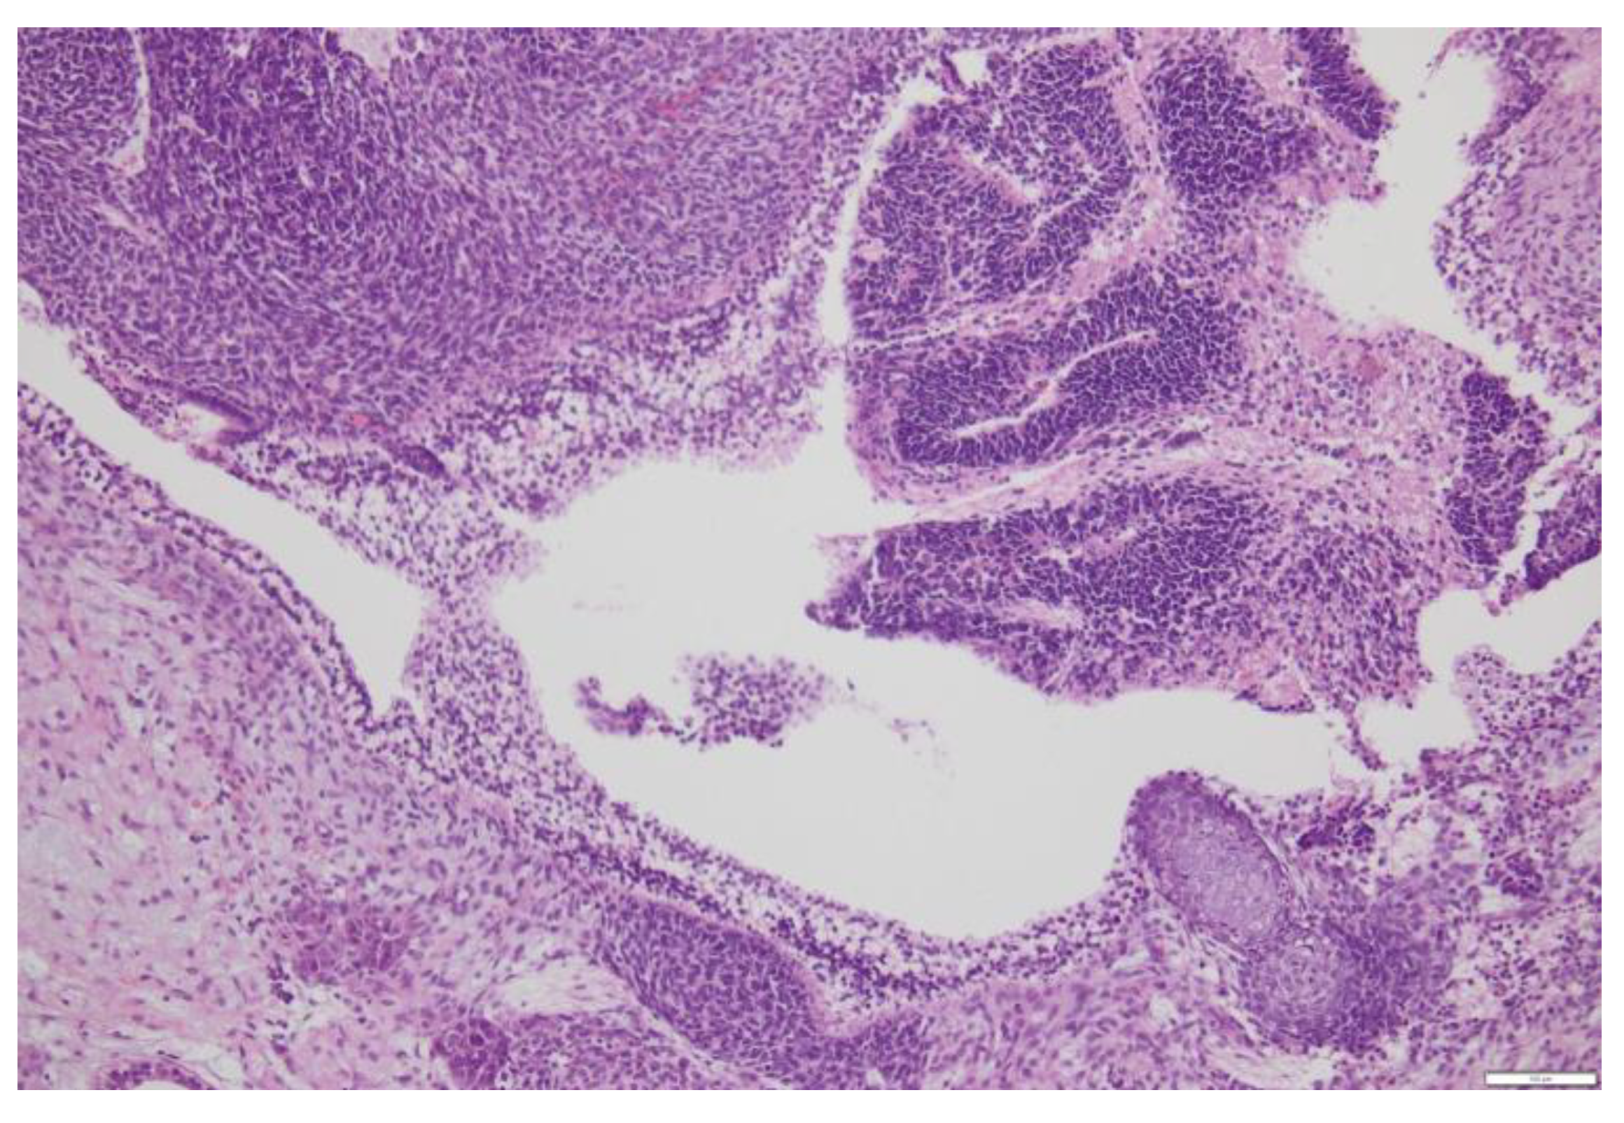

3. Immature Teratomas

3.1. Diagnosis

3.2. Prognostic Factors

- Grade 1: < 1 low power field (using a 4x objective and a 10x lens, 40x of magnification) per slide;

- Grade 2: ≥ 1 but < 3 low power fields in any slide;

- Grade 3: ≥ 3 low power fields in any slide.